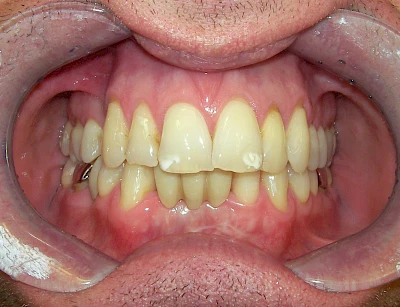

Manche Medikamente wie zum Beispiel das Antibiotikum Tetrazyklin kann bei Einnahme im Zeitfenster der Zahnentwicklung auch irreversibel in die Zahnsubstanz. eingelagert werden. Tetrazyklin verfärbt die jeweils betroffenen Zähne bläulich und sollte deshalb während der Schwangerschaft und bei Kindern nicht verordnet werden.

- Durch Medikamente während der Zahnreifung (einzelne Zähne auf beiden Seiten, z. B. bläulich durch Antibiotikum Tetrazyklin)